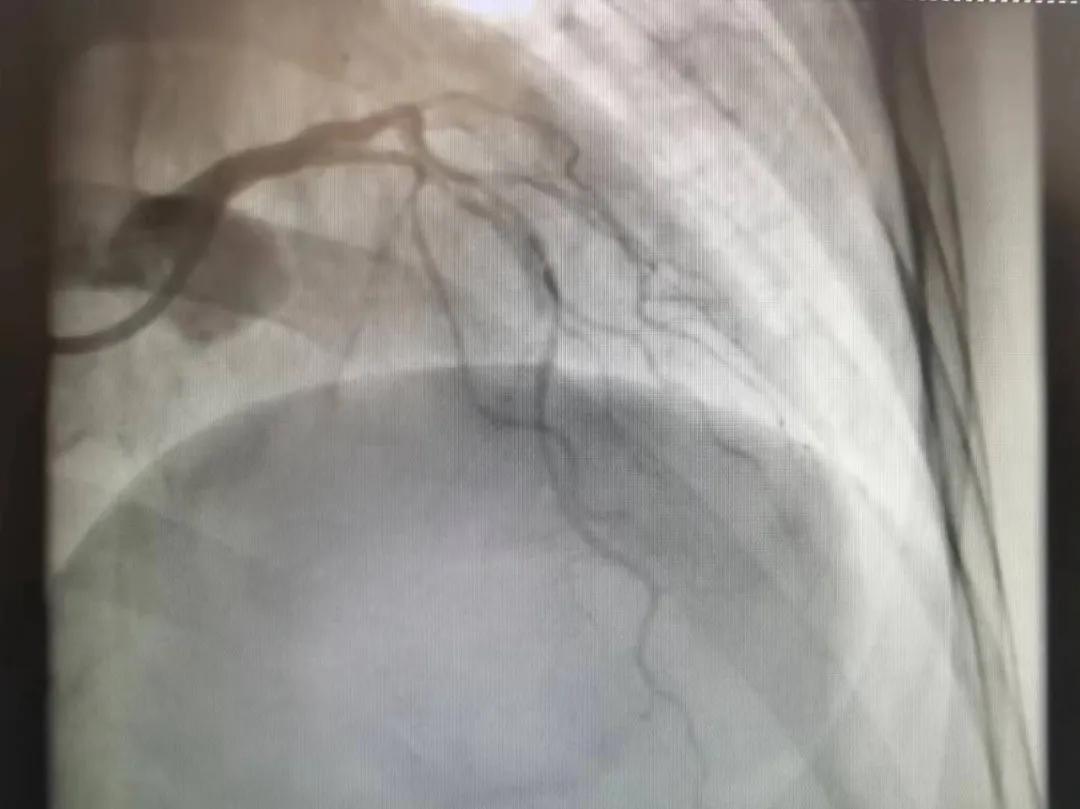

病人是位六十多歲的女性患者,有長期高血壓病史,1個月前開始出現(xiàn)胸悶胸痛,口服藥物治療效果不佳,經(jīng)朋友介紹,來到市二院心血管內(nèi)科。入院后完善冠狀動脈造影提示:前降支全程彌漫性狹窄伴鈣化,最重95%,回旋支狹窄約85%,右冠脈全程狹窄伴鈣化,最重60%。血管內(nèi)超聲顯示右冠脈開口面積3.36mm²,可見環(huán)形鈣化,考慮患者病變程度重、鈣化明顯,常規(guī)器械無法實現(xiàn)病變的良好預(yù)處理,且有很高的冠脈穿孔、血管夾層的風(fēng)險。

術(shù)前